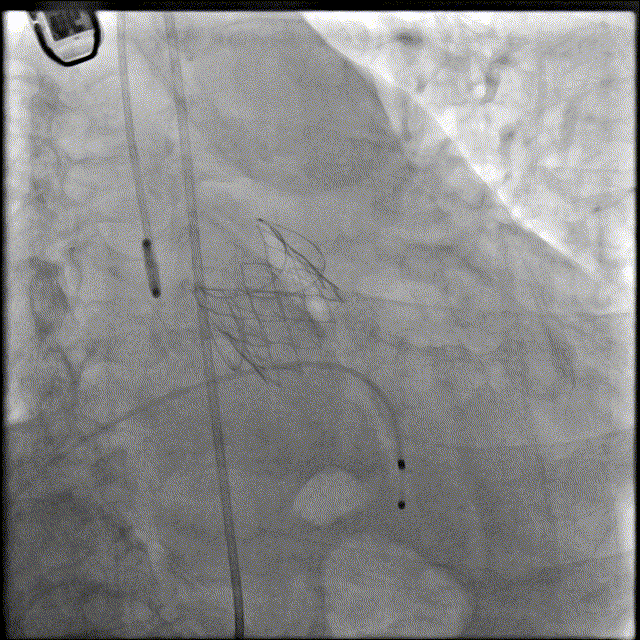

术后瓣膜形态良好

术中使用22mm杰成经血管介入瓣膜,顺利完成手术,经超声评估患者跨瓣压差等指标较术前明显改善。患者恢复状况良好,术后第一天便顺利出院。